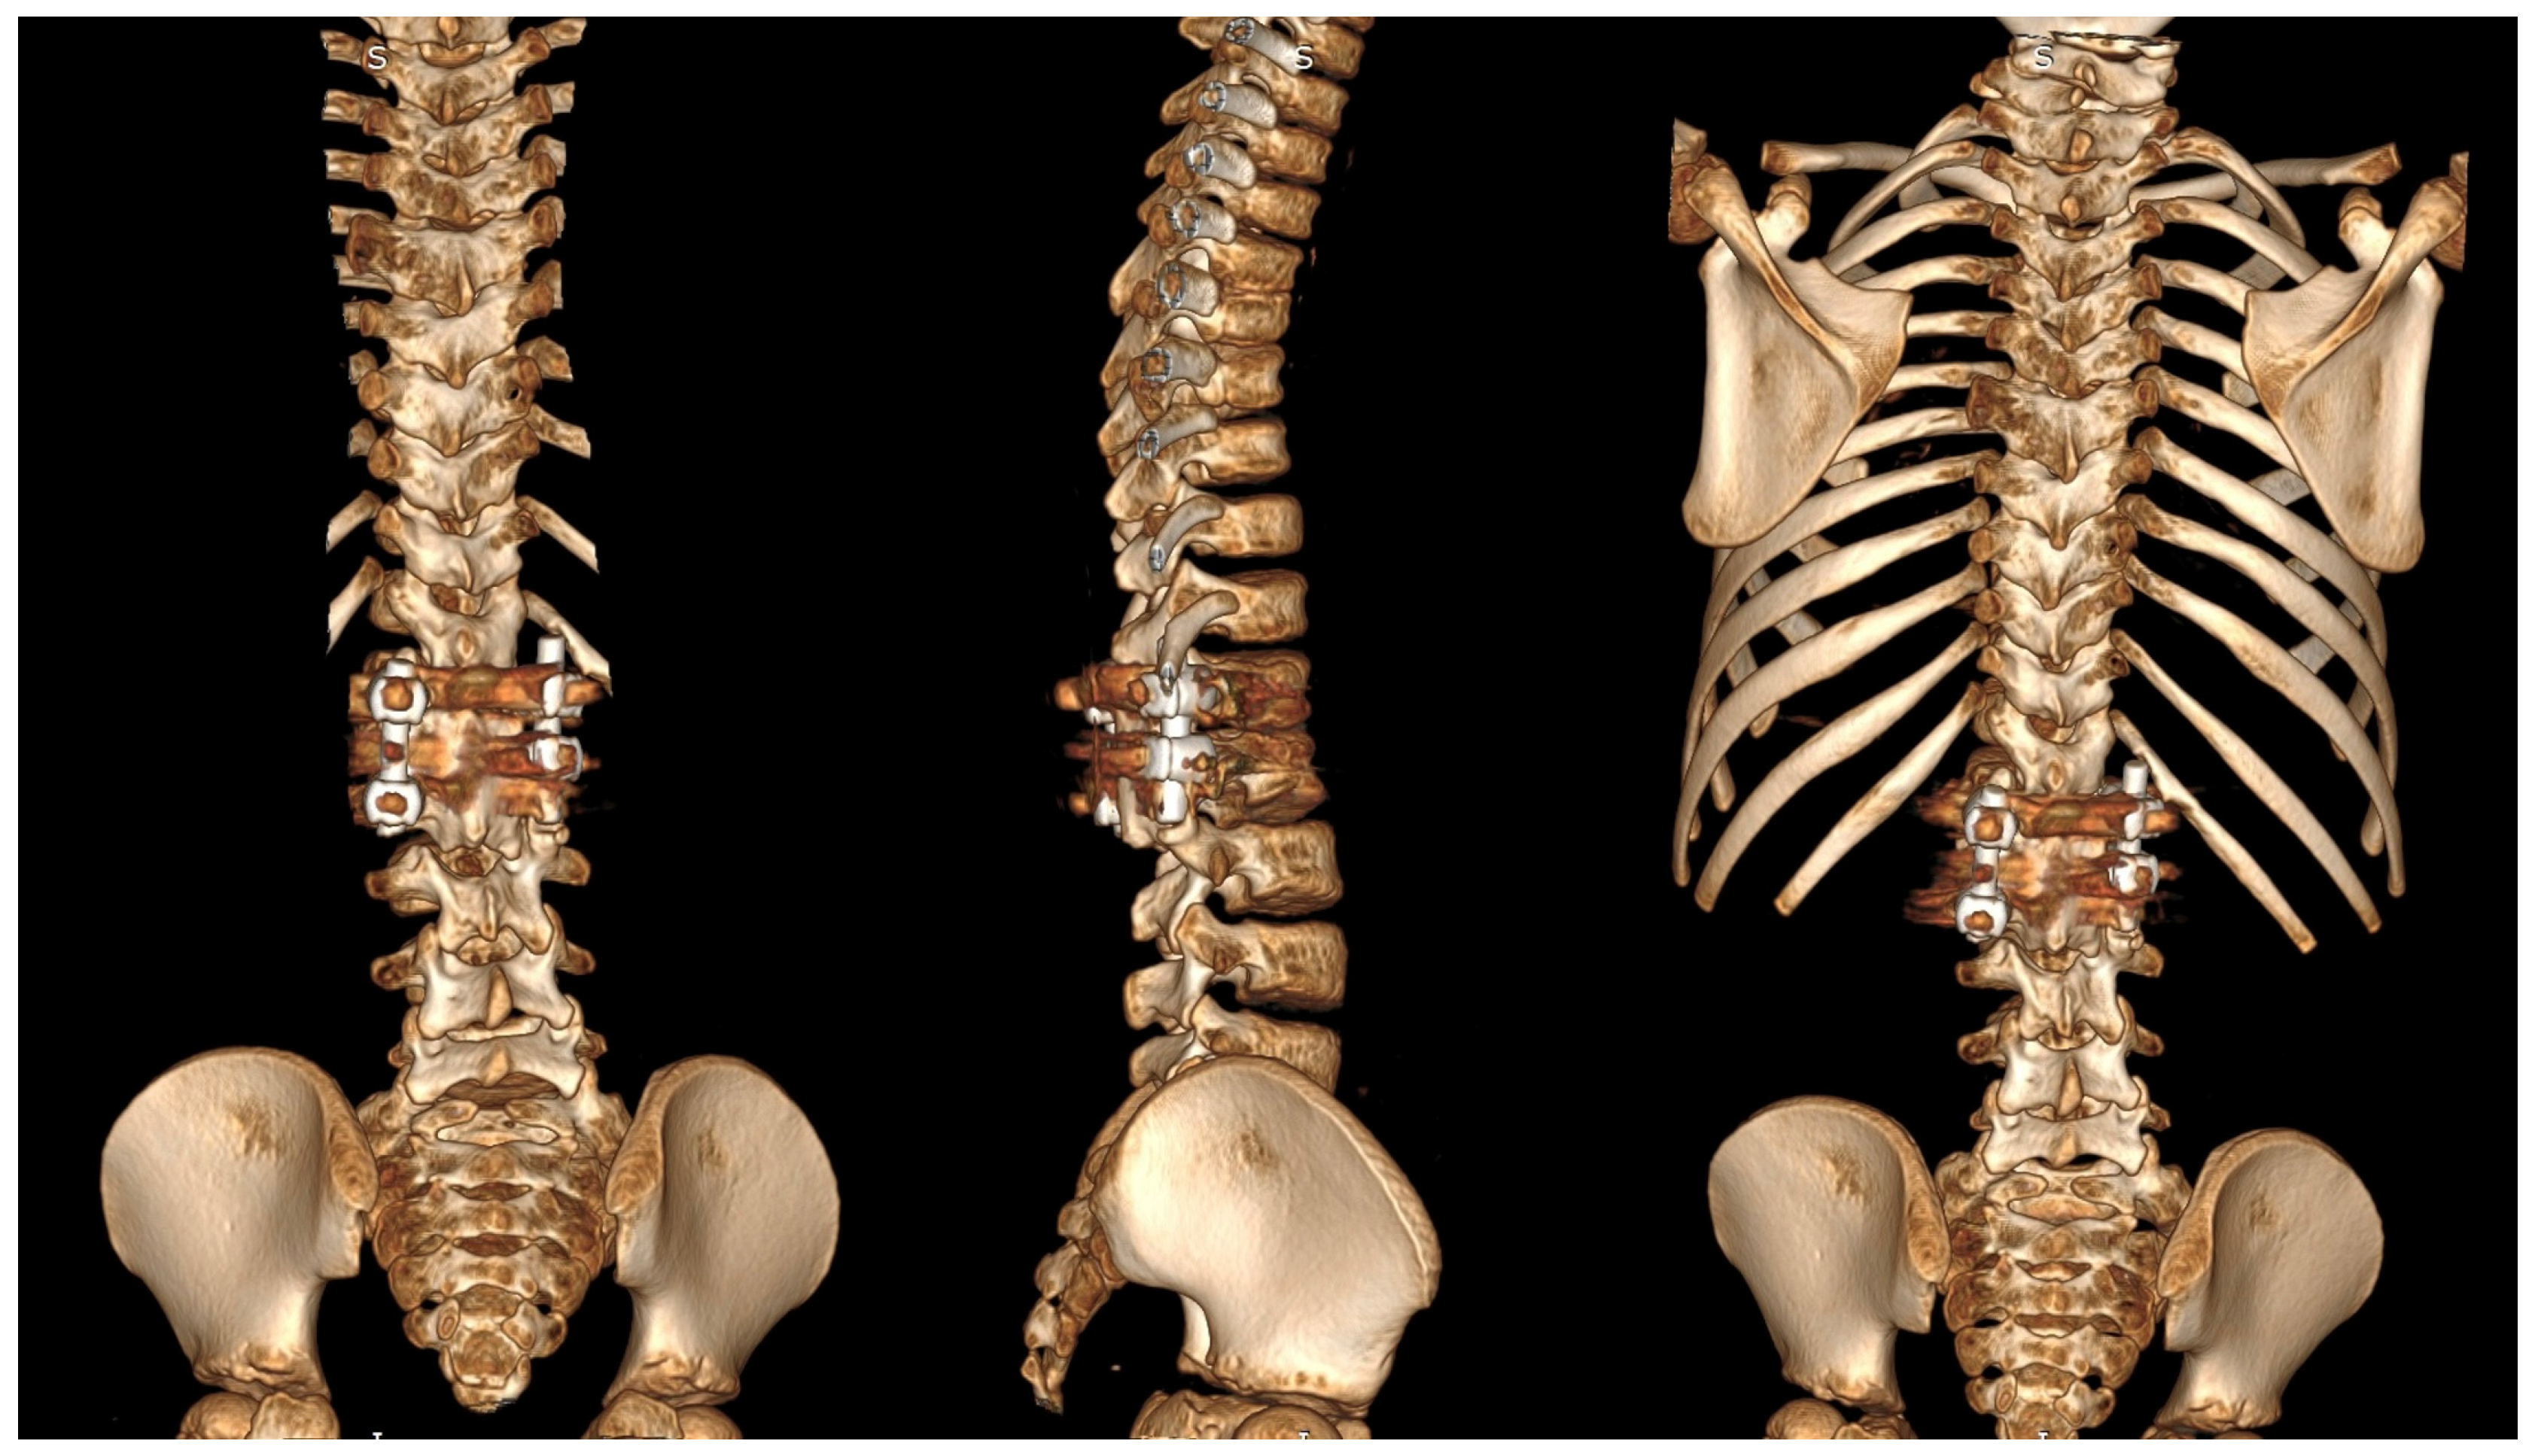

6.2. Advanced Imaging Modalities

7.3. Surgical Techniques

7.3.3. Hemivertebrectomy

8. Complications and Risk Management